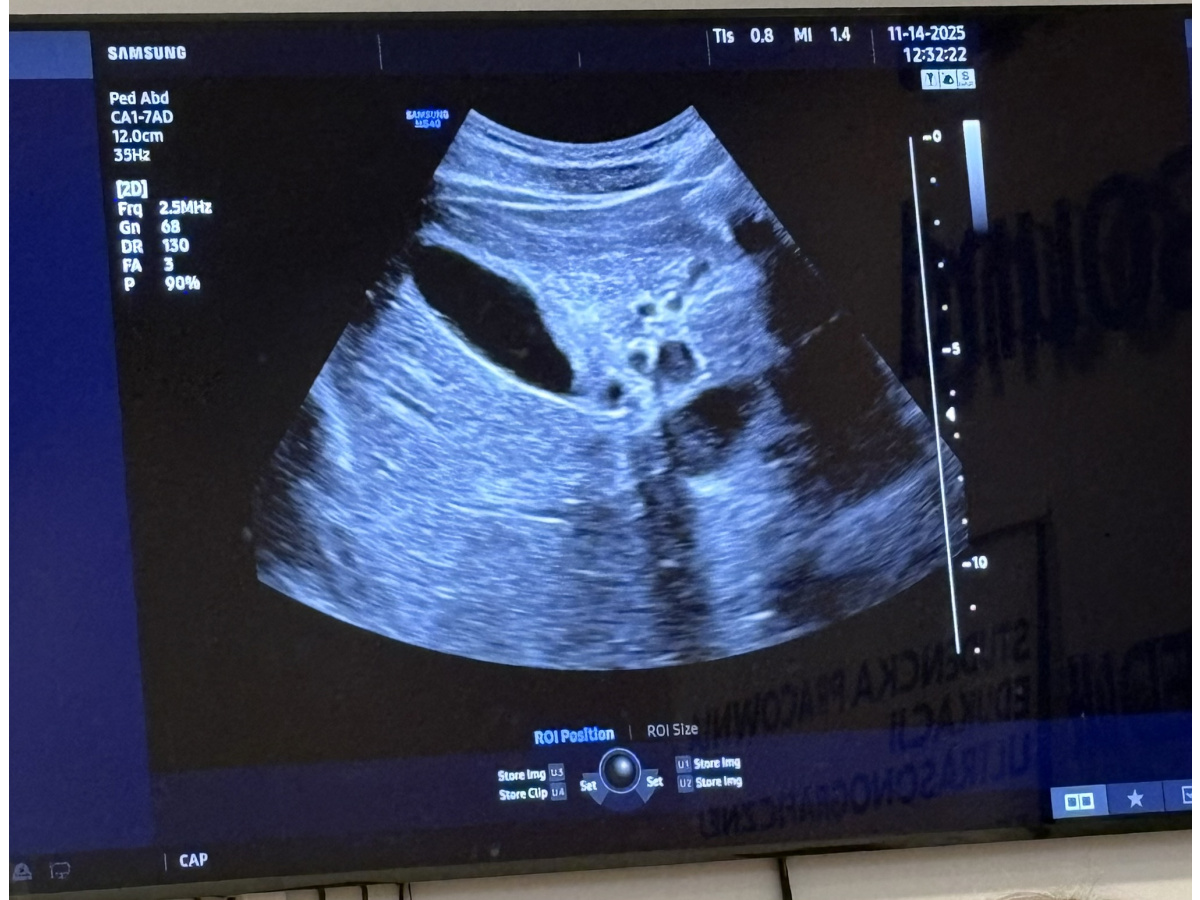

Podstawy badania USG - co naprawdę widzi lekarz.

Uczniowie też zobaczyli: jak to działa; co tam widać; jak to zrobić, żeby coś zobaczyć. Nauka i praktyka w rękach uczniów.